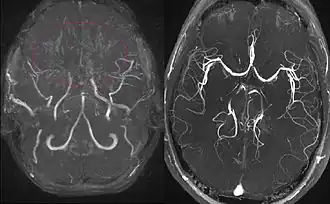

Left: MIP reconstructed MR angiography of a 11-year-old girl with moyamoya disease.

Right: healthy patient, for comparison.

Magnetic resonance angiography (MRA) is also useful in diagnosing the disease with good correlation with Suzuki's grading system.[12]